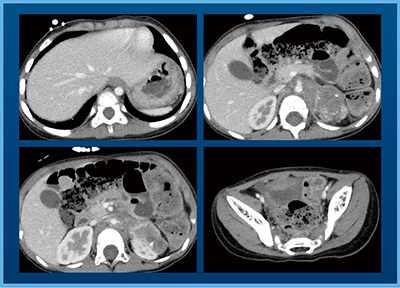

症例2は,2歳,女児,肝芽腫術後,化学療法後で,やはり造影1相のみで十分な情報が得られている(図5)。

図5 症例2:肝芽腫術後・化学療法後(2歳,女児)